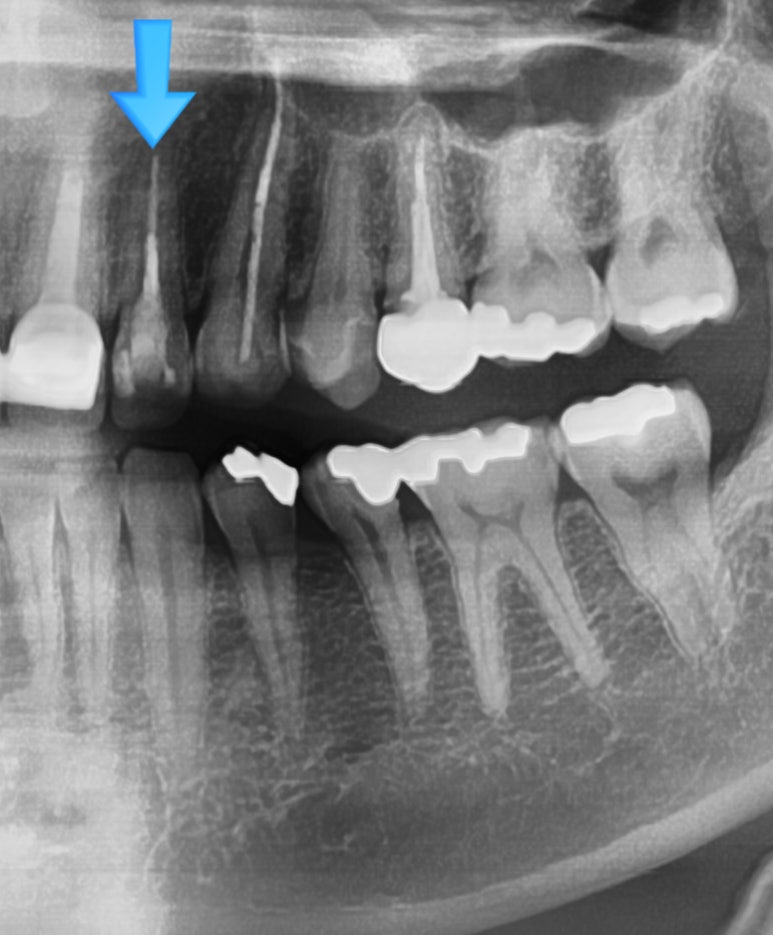

기존에 다른 치과에서 치료받은 치아가 부러진 상태로 오심 (부러진 머리를 끼워서 오셨으나 제거하고 찍은 상태)

네비게이션 임플란트를 통해 정확한 각도로 식립하고자 함

임플란트 전 후 사진

저희 연세예감치과가 시청역에 위치하다보니

시청역 직장인들이 전날 저녁에 사고로 이가 흔들리고는

다음날 아침에 오는 경우가 많습니다. (회사에 출근은 해야하니까요...)

회사에 출근 잠깐 하고 치과로 오시는데, 보통 나이 지긋하신 남자 임원분들이 이가 없이 직원들을 만나기는 민망하시겠죠.

일단 다시 회사 복귀할 수 있게 임시치아도 일단 만들어 붙여드리고,

임시치아로만 계속 계실 수는 없으니 조만간 들어갈 수 있게 임플란트 준비도 하게 됩니다.

이 분 같은 경우는 남은 뿌리를 빼면서 동시에 발치즉시 임플란트를 하셨습니다.